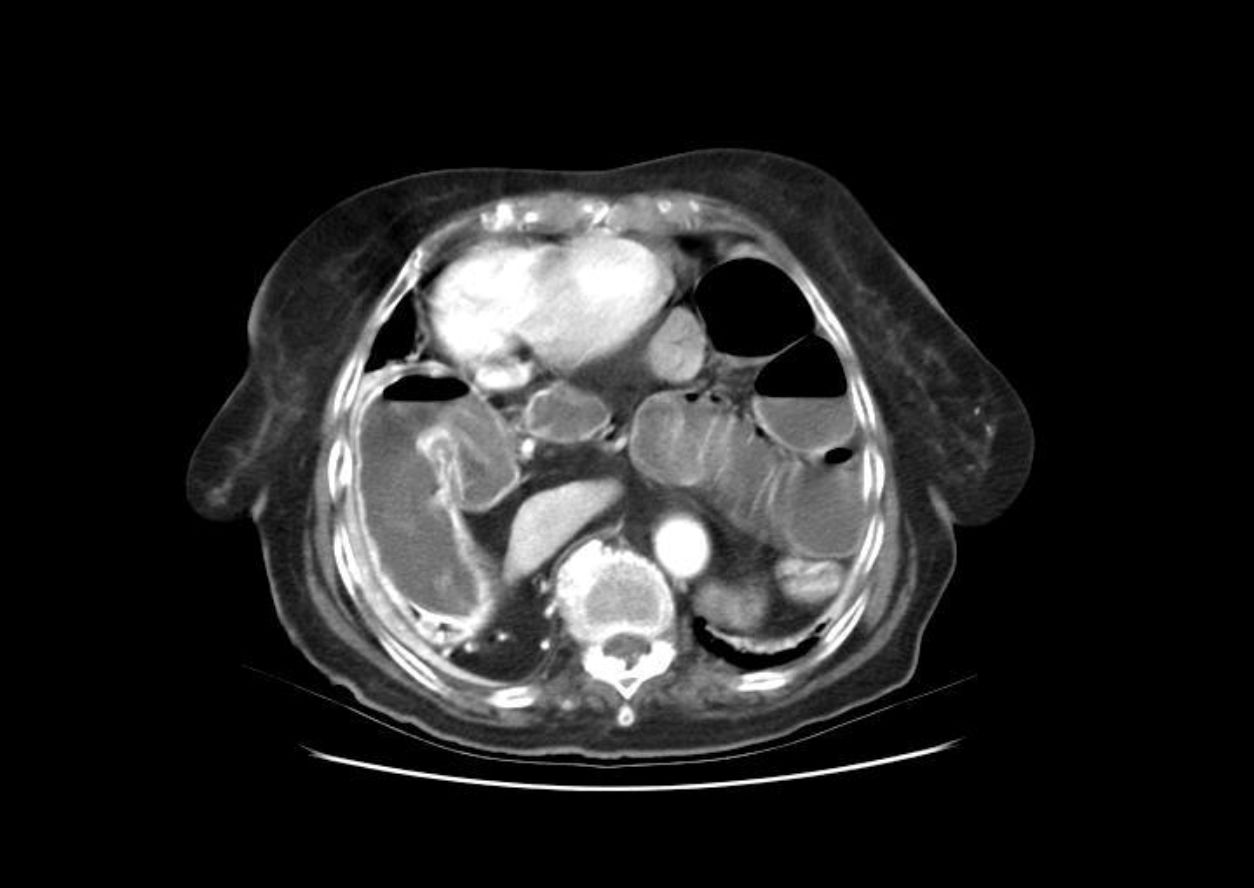

La verdad es que este caso es muy difícil de describir y etiquetar, por ello admito todo tipo de comentarios y críticas al respecto. Después de darle muchas vueltas al caso y repasar bastante bibliografía, creo que realmente la paciente padece un cuadro complejo de volvulación crónica gástrica de tipo mixto (quizás con predominio organoaxial), donde el pólipo situado en la zona teórica del antro ejerece un efecto valvular que dificulta la salida gástrica y podría ser responsable de parte de los síntomas de intolerancia alimenticia que padece la enferma. Y digo esto último porque es curioso que hasta que acudió a urgencias con dolor abdominal subagudo, y el cuadro de malnutrición nunca había tenido síntomas de este tipo previamente.

Los vólvulos gástricos tal y como los conocemos (formas agudas) son entidades muy poco frecuentes que constituyen una urgencia quirúrgica en la mayoría de los casos. Existen 2 tipos según se produzca una rotación de la víscera en su eje mayor (rotación organoaxial) o en el menor (mesentéricoaxial). No obstante, las formas incompletas con una rotación < 180º son bastante mas frecuentes de lo que se piensa y pueden manifestarse con síntomas inespecíficos como nauseas, vómitos y dolor epigástrico. También tienen una mayor predisposición a la volvulación aguda. Algunos autores denominan estas formas vólvulos crónicos, aunque otros simplemente las llaman posiciones anómalas organoaxiales o mesentérico axiales. Las formas mixtas no son excepcionales. El tipo mas común de vólvulo es el organoaxial que en los pacientes > 65 años está en muchas ocasiones asociadas a hernias hiatales, sobre todo paraesofágicas. La causa de la volvulación parece estar relacionada con la laxitud de las estructuras de fijación de la cámara gástrica en el abdomen. El tratamiento de las formas agudas, sobre todo si hay estrangulación e isquemia con riesgo de perforación es la cirugía por vía laparoscópica. No obstante hay descritos casos en la literatura de desvolvulaciones endoscópicas que permiten (como en el colon) una cirugía electiva en mejores condiciones clínicas.